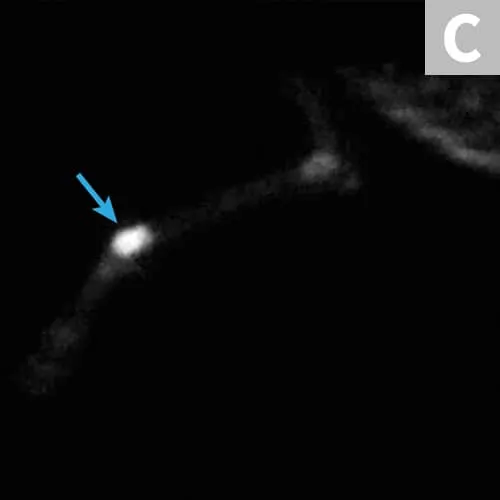

Osteosarcoma (OSA) is the most common primary bone tumor in dogs.5 Unfortunately, most cases are not cured with surgery because of the high risk for metastatic disease.5 Patients should be staged for gross metastasis to lung or another bone before surgery (Figure 2). Staging methods vary depending on clinician preference, but 3-view thoracic radiographs and/or thoracic CT and bone scan are recommended.6 Limb amputation is the most commonly performed surgical treatment; major benefits include removal with wide margins of the tumor, removal of the source of pain, and removal of potential for ongoing metastasis.

(A) Radiograph of a distal radial osteosarcoma. Centered at the distal metaphysis of the radius, there is evidence of permeative and moth-eaten lysis. There is also concurrent ill-defined periosteal proliferation consistent with an aggressive bone lesion. (B) CT scan of distal radial osteosarcoma in the same patient. Coronal view of limb in bone window. There is more evidence of geographic bone lysis and evidence of periosteal proliferation. Consistent with an aggressive bone lesion. (C) Bone scan of the distal radial osteosarcoma in the same patient. Note the increased uptake of radiopharmaceutical in the distal radius of the patient (arrow).